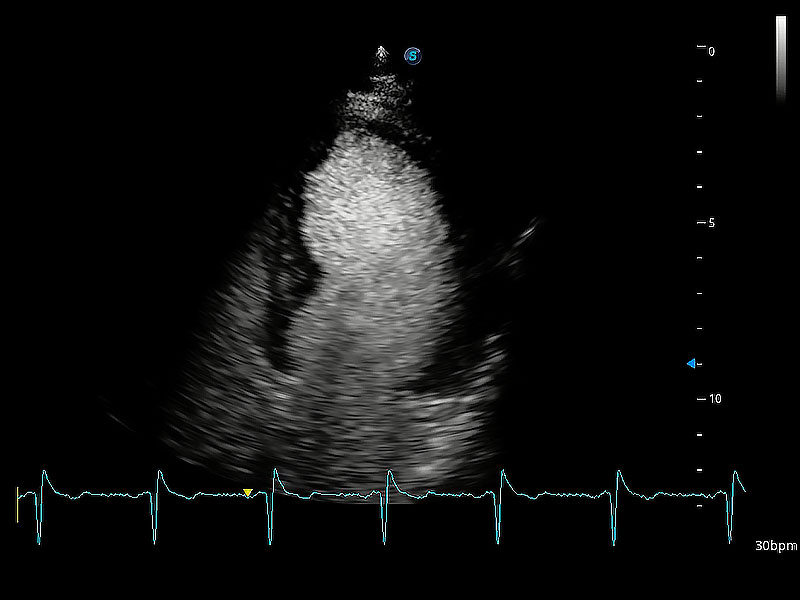

ProPet 80 配備了豐富的心臟探頭群、先進(jìn)的成像技術(shù)和專(zhuān)業(yè)的心臟測(cè)量工具,可幫助動(dòng)物醫(yī)生為不同體型和生理結(jié)構(gòu)的動(dòng)物提供心臟和心肌功能的全面評(píng)估。

能夠基于左心室壁追蹤和辛普森法,自動(dòng)計(jì)算射血分?jǐn)?shù),支持多個(gè)可移動(dòng)點(diǎn)描跡,與手動(dòng)測(cè)量相比,極大節(jié)省了動(dòng)物醫(yī)生的時(shí)間和精力。